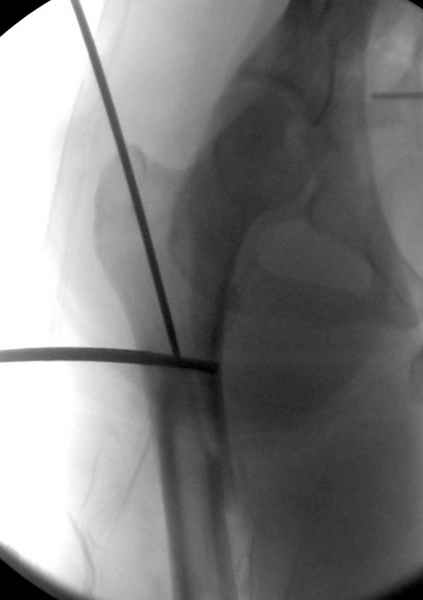

Как раз недавно у меня был примерный случай: больному 36 лет, поступил ночью, травма в результате мотоциклетной аварии, кроме чрезвертельного и спирального перелома левого бедра имеется переломы костей предплечья с этой же стороны. Скелетное вытяжение, а на следующий день больной про оперирован на ортопедическом столе с дистракцией. Чтобы не расколоть чрезвертельный перелом провели временную спицу ближе к переднему кортексу, из малого разреза костодержатель для репозиции, а фиксацию провели антиградным штифтом. Этапы операции на снимках.

Джолдас Кульджанов